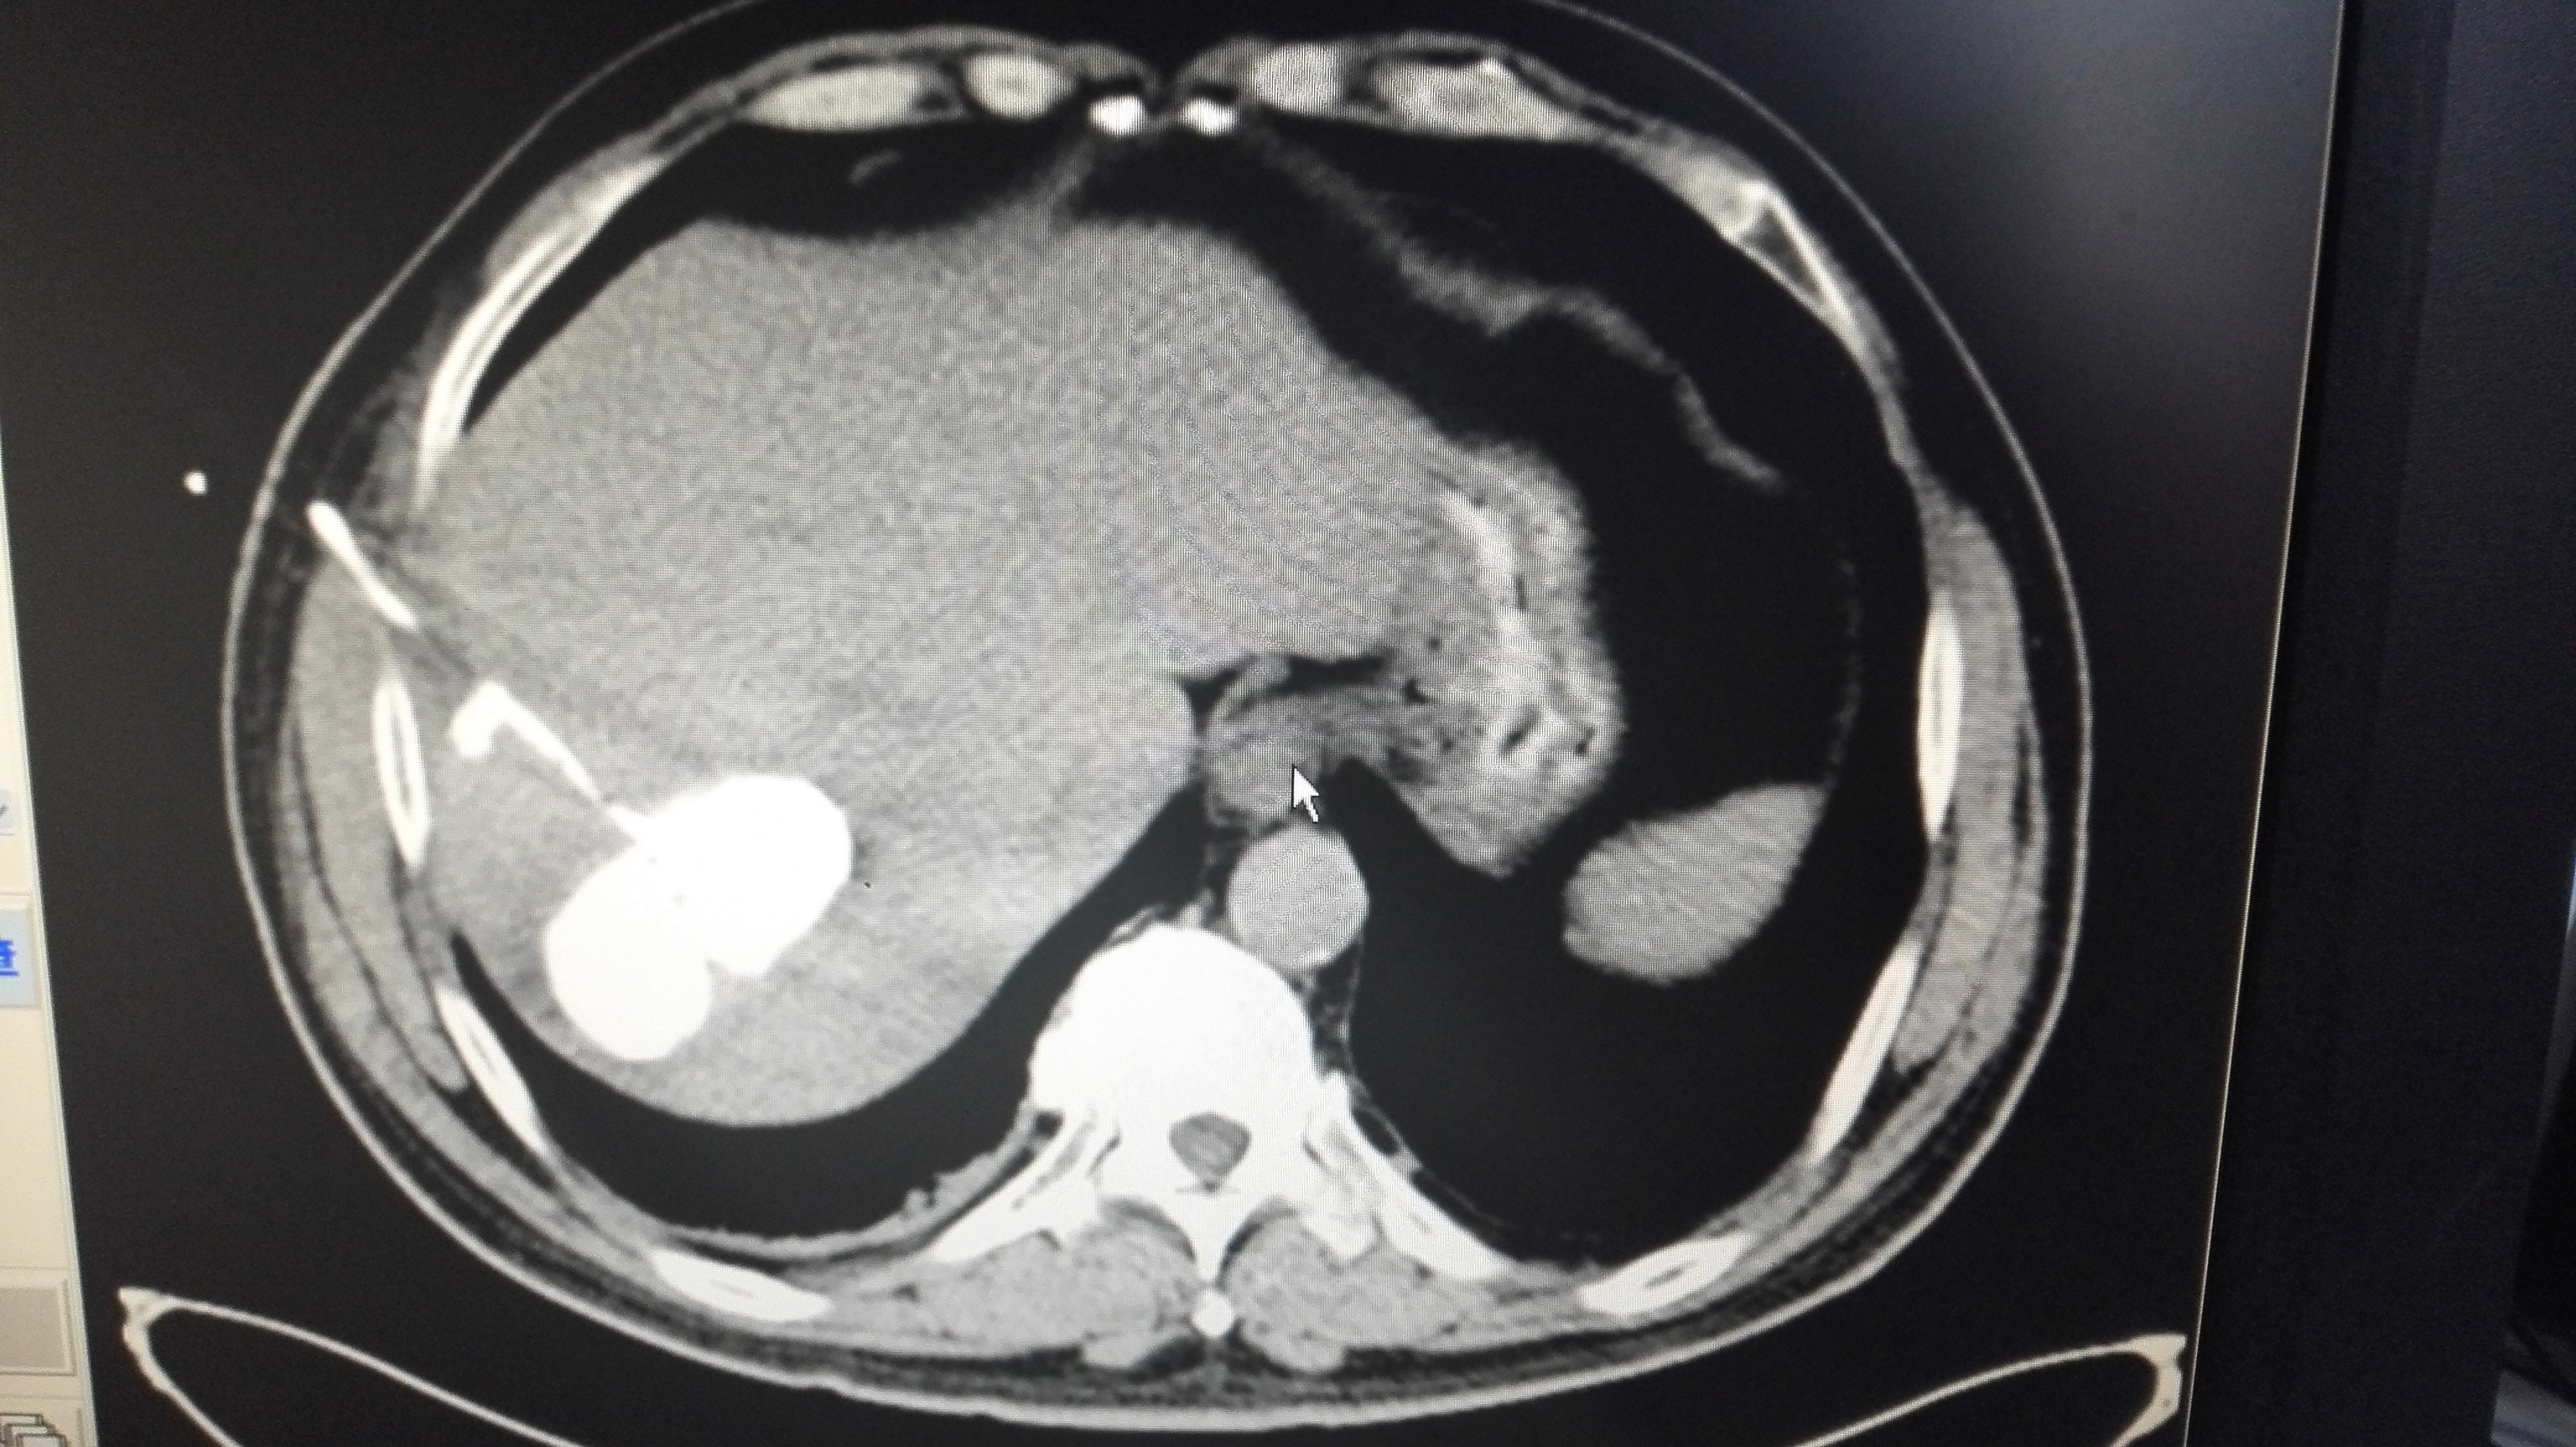

肝囊肿怎么治?聚桂醇硬化治疗帮您忙 - 好大夫

4160x2336 - 1674KB - JPEG